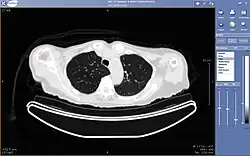

Coupe axiale d'un scanner visualisée à l'aide du logiciel Keosys, une société spécialisée dans la télémédecine.

La téléradiologie consiste en la consultation et l'interprétation d'images radiologiques ou échographiques à distance.